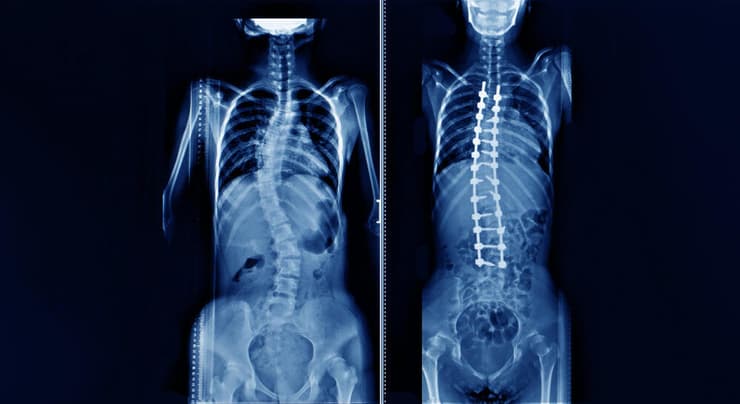

"עקמת (סקליוזיס) היא מחלה תלת-ממדית שפוגעת בעמוד השדרה שמתחילה בדרך כלל עם תהליך הצמיחה של הגוף בתחילת גיל ההתבגרות", מסביר ד"ר איל ברבלק, אורתופד ומנתח גב בבית החולים אסותא רמת החייל. "היא מתאפיינת בעיקר על ידי עיוות בעמוד השדרה הגבי ועמוד השדרה המותני. במקום שעמוד השגרה יהיה ישר כשאתה מסתכל עליו, צורתו הופכת לצורת S, צורה של נחש. העקמת היא גם מחלה רוטטורית - מחלה סיבובית - היא גורמת לרוטציה של החוליות ויוצרת גיבנת לרוב בשכמה הימנית, וגיבנת נוספת בעמוד השדרה המותני מצד שמאל. היא נפוצה יותר בבנות מתבגרות הרבה יותר מאשר במתבגרים, ביחס של שש לאחת. כלומר, על כל שישה מקרים של בנות, יש מקרה אחד של עקמת אצל בנים".

לדבריו, הכאבים אינם בהכרח חריפים, אך בהחלט מורגשים. "הם לא קשים, אבל מציקים למטופלת. בגללם היא באה לאמא ולאבא. ההורים מסתכלים, רואים שהגב לא סימטרי, וכך מגיעים לבדיקה אצל הרופא". מכאן האבחון עצמו מתחיל בבדיקה קלינית פשוטה. "אנחנו מתחילים על ידי זה שאנחנו מסתכלים על הגב, מבקשים מהמתבגרת להתכופף קדימה", מסביר ד"ר ברבלק. "התכופפות קדימה של הגב מחמירה את העקמת, ואנחנו מודדים. יש לנו מכשיר מאוד פשוט שנקרא סקוליומטר, ששמים על הגב של המטופלת, ואיתו מודדים את הזווית בבדיקה הגופנית אצל הרופא. אם יש חשד לעקמת - או שהסקוליומטר מראה חשד לעקמת, או שהתבוננות מראה חשד לעקמת – אנו שולחים לצילומי רנטגן פשוטים. הצילומים מאפשרים לנו למדוד כמה קשה העקמת ולהתוות טיפול".

לאחר השלמת הבדיקות, מתקבלת ההחלטה הטיפולית בשיחה משותפת עם המשפחה. "אם העקמת היא פחות מ-20 מעלות - היא לא צריכה טיפול, רק מעקב. באים כל חצי שנה עם צילומים חדשים ומסתכלים שהעקמת לא מחמירה. אם היא מעל 20 מעלות אנחנו מתחילים טיפולים שמרניים: פיזיותרפיה בשיטת שרוט ומחוך, שיטות טיפול שמרניות המנסות לעצור את ההתקדמות של העקמת", הוא מפרט. "אם העקמת מגיעה ל-50-40 מעלות ועדיין יש פוטנציאל גדילה מתחילים לחשוב על טיפולים ניתוחיים. אם העקמת היא 50-40 מעלות ואין פוטנציאל גדילה - לא חייבים לנתח".

הוא מוסיף: "אנחנו יודעים שאם העקמת עברה את ה-50 מעלות, גם כאשר הגענו להתבגרות מלאה, כל שנה העקמת עלולה להחמיר במעלה עד מעלה וחצי עד לשארית החיים. ולכן שמטופלת בת 15 הגיעה למעל 50 מעלות בדיוק על גבול הניתוח, וזה מחמיר כל שנה, בגיל 40-30 היא תגיע ל-80-70 מעלות עקמת עם פגיעה מאוד משמעותית באיכות החיים. בגלל זה, את העקמות האלו אנחנו עוצרים ומדברים על ניתוח".

באשר לניתוחים, ד"ר ברבלק מונה מספר שיטות ומתחיל בשיטה הקלאסית - ניתוח בגישה אחורית. "מבצעים חתך עורי בגב, ומכניסים ברגים ומוטות. הברגים מוחדרים תחת ניווט לתוך הגב, והמוטות ננעלים לראשי הברגים ובעצם מקבעים את עמוד השדרה. זה ניתוח קלאסי, והוא ניתוח מצוין".